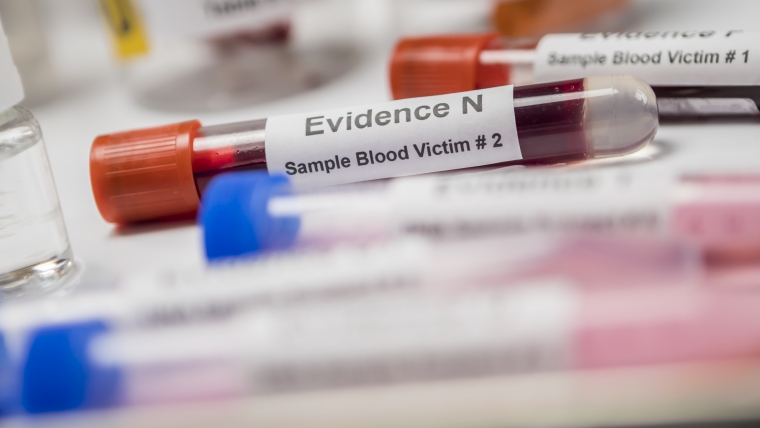

Las pruebas de sangre se usan para medir o analizar células, sustancias químicas, proteínas y otros componentes de la sangre. Son uno de los tipos más comunes de pruebas de laboratorio.

La prueba de PSA (antígeno prostático específico) mide el nivel de PSA en la sangre.

Estudio, diagnóstico, tratamiento y prevención de las enfermedades de la sangre y los órganos que participan en su producción.